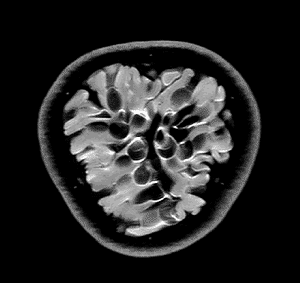

Quizás no sea lo más ortodoxo, pero no podemos negar su componente curioso y llamativo. Seguramente pocos nos imaginaríamos que una fruta de la pasión o la raíz de un apio tienen en su interior un aspecto muy similar al del cerebro. O que las fresas se parecen a un panal de miel. Aclaremos el misterio: esto ocurre cuando las frutas son observadas a través de una resonancia magnética.

Andy Ellison, técnico en resonancias magnéticas del Centro de Imágenes Biomédicas de la Escuela de Medicina de la Universidad de Boston, se ha propuesto enseñarnos de este modo cómo son las entrañas de las verduras y las frutas que comemos a diario. Para ello, ha utilizado la tecnología médica avanzada con la que trabaja para capturar las secciones transversales de estos alimentos, de la misma manera que cada día se hace con el cerebro humano, las rodillas o la columna.

El resultado, que recoge en su blog Inside Insides, son unas fascinantes imágenes y GIFs que nos muestran las frutas y las verduras desde otro punto de vista. Desde un interior tan llamativo y adictivo como lo pueden ser sus colores, formas y sus texturas. La colección es amplia y da para todo tipo de evocaciones, porque por el escáner de Ellison –en concreto, una Philips 3 Tesla MRI, explica– han pasado todo tipo de alimentos, desde los más comunes como las cebollas, los pimientos, los tomates o los plátanos, hasta lichis, la jaca (también conocida como jackfruit, uno de los frutos más grandes del mundo), la fruta del dragón o el kiwano (o pepino africano).